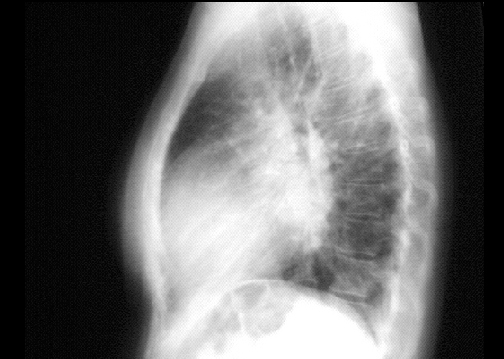

Lateral view

In the lateral view, left atrial enlargement is further reflected by the prominent posterior left atrial shadow. Right ventricular enlargement is best seen in this view and is manifested by obliteration of the retrosternal air space.